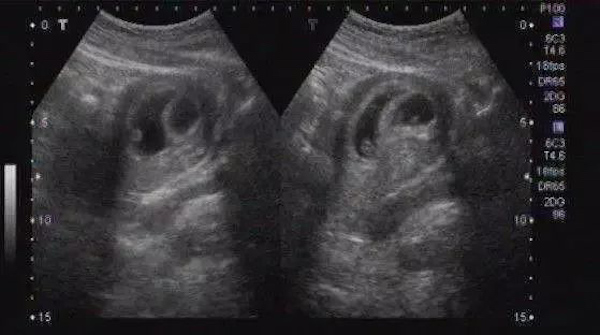

早孕期孕囊里包裹的除了胚芽还有一些羊水。我们可以想象一下,兜着水的气球,放在桌子上会变成什么形状。孕囊就是这种不规则的类椭圆体。

孕期,不管是腹壁B超还是经阴道B超,都是无法做到三维重建,只能根据超声检测到的2-3个径线来描述孕囊的大小。大家拿到手的B超报告,数值接近的,容易被理解为是圆形,有的数值差距太大,就被理解为椭圆形。

这个和男女半毛钱关系都没有,只是超声扫描到的切面不同测到的数值不同而已。比方说,一枚鸡蛋或者一颗扁扁的桔子。我们从不同的方位用灯光照射,看看投影都有神马形状:圆形、扁的、椭圆……正所谓横看成岭侧成峰,远近高低各不同。